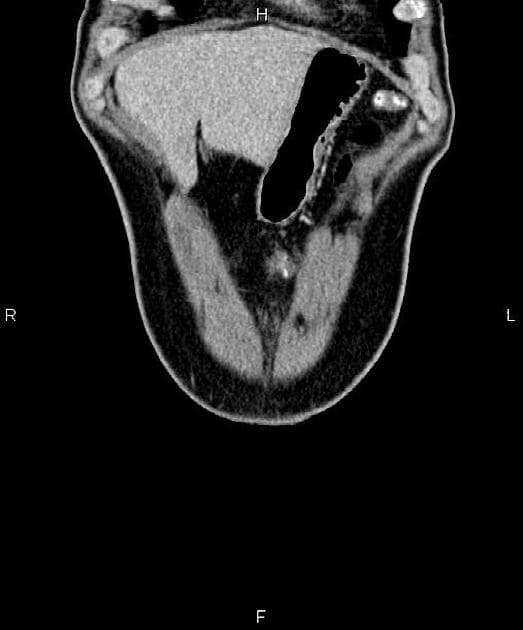

Tụy

Có khối kích thước 3 x 2 cm ở đầu tụy, tăng quang chậm và tiến triển, giảm tăng quang so với phần còn lại của tụy. Ống tụy chính phía trên giãn nhẹ, có hiện tượng tắc đột ngột như thấy trên MRCP gần đây. Không có vôi hóa tụy. Không thấy hình ảnh tắc mật (no evidence of biliary obstruction).

Khối lan xuống dưới vào mạc treo ruột non. Có hẹp nặng khu trú động mạch mạc treo tràng trên (SMV). Tiếp xúc giữa khối và SMV trên đoạn dài 42 mm. Tiếp xúc giữa khối và tĩnh mạch cửa trên đoạn dài 25 mm. Có xâm lấn nhánh tá tràng đầu tiên và thứ hai. Trục tạng, động mạch gan, động mạch mạc treo tràng trên thông thoáng. Động mạch vị tá tràng (GDA) bị bao quanh.

Các nốt nhỏ 4 mm thấy trong mạc treo ruột non. Không có hạch bất thường khác về kích thước hay hình thái ở ổ bụng hay vùng chậu.

Gan có tình trạng xâm nhập mỡ lan tỏa dạng địa lý. Không có di căn gan. Có adenoma tuyến thượng thận trái giàu lipid, kích thước 20 mm. Đây không phải là di căn. Tuyến thượng thận phải bình thường.

Sẹo khu trú ở thận phải. Các nang vỏ thận nhỏ. Không có khối đặc ở thận. Lách hình dạng bình thường. Không có dịch tự do. Ruột non và đại tràng hình ảnh không bất thường. Xương thấy trên phim bình thường. Thoái hóa khớp cùng chậu thắt lưng.

Hình ảnh học gợi ý ung thư biểu mô tuyến đầu tụy (pancreatic head adenocarcinoma), về mặt giải phẫu ở mức giới hạn có thể cắt bỏ được do có xâm lấn SMV và các nhánh tá tràng.

Ung thư biểu mô tuyến tụy - có thể cắt bỏ được ở mức giới hạn (borderline resectable)